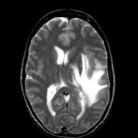

The reconstructions of a 256×256256256256\times 256 brain image from its radial samples acquired with a 40 spoke trajectory are shown in Fig. 6. The measurements are corrupted with zero mean complex Gaussian noise of standard deviation σ=18.8𝜎18.8\sigma=18.8. All methods result in loss of subtle image features since the acceleration factor and the noise level are high. We observe that the NLS scheme provides better recovery than the competing methods. The quantitative results in this setting for various MR images are shown in the bottom section of Table IV. We observe that the SNR improvement offered by NLS over the other methods are not as high as in the previous cases, mainly due to the considerable noise in the data and the high acceleration.

Refer to caption

(a) Original

(b) DLMRI,SNR=17.46

(c) TV,SNR=17.43

(d) NLS,SNR=18.46

(e) Sampling pattern

(f) DLMRI error

(g) TV error

(h) NLS error

Figure 6: Comparison of the algorithms in the presence of noise. We consider the recovery of a 256×256256256256\times 256 original MRI brain image from its radial trajectory with 40 spokes, contaminated by Gaussian noise with standard deviation σ=18.8𝜎18.8\sigma=18.8. The error images are magnified by a scale of 5 fold for the best visibility. This is a challenging case due to the high undersampling factor and high measurement noise. We observe that the NLS scheme provides the best overall reconstructions.